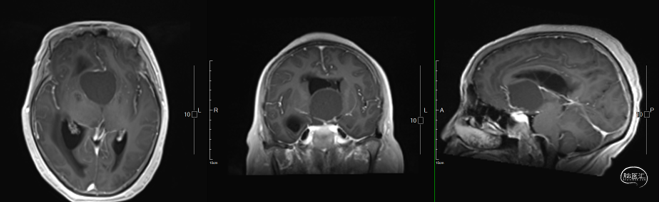

术后影像学

头部MRI提示:影像学全切,脑积水得到明显好转,实性部分未见显影,垂体组织保留良好。

造釉细胞型颅咽管瘤

术后激素经外源性皮质醇补充,未见明显下降,由静脉逐步过渡至口服,患者出院前未服用泼尼松片情况下,皮质醇水平正常。

术后患者Na+呈现先上升后下降过程,经过预判性予以动态调控,患者电解质逐步趋于稳定,未出现明显严重低钠血症。